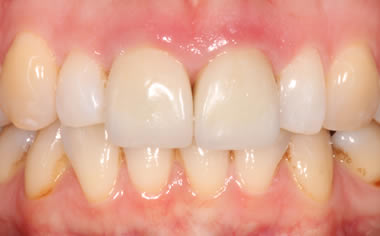

More front teeth replaced by dental implants

Case Three (4 images)